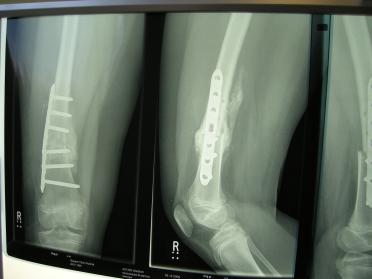

XRays